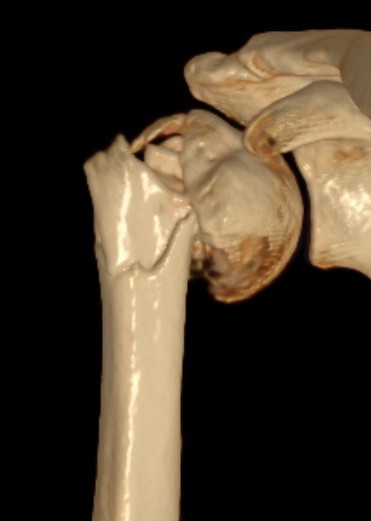

Young patients

- displaced proximal humerus fractures

Elderly patients with likely poor outcomes

- 100% displaced fractures unlikley to heal

- fracture dislocations

Displaced 2 part SNOH fractures in young patient